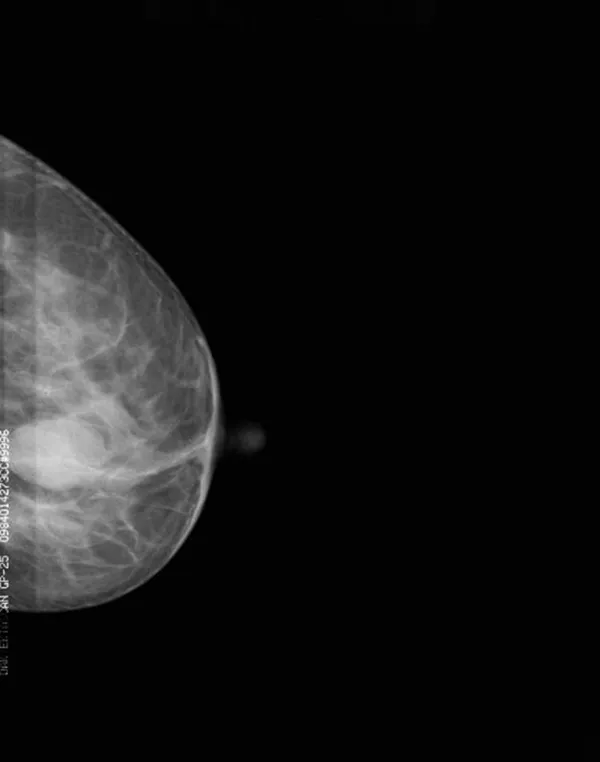

Imagen de un Tumor Imagen de un Tumor

Este modelo de mamógrafo digital ha sido desarrollado para brindar una herramienta precisa y eficaz en la detección y diagnóstico de enfermedades mamarias. Incorpora un detector plano digital y un tubo de rayos X de molibdeno de fabricación italiana (IAE), lo que permite obtener imágenes de alta resolución capaces de identificar microcalcificaciones de hasta 0.1 mm, fundamentales en la detección temprana del cáncer de mama. Está equipado con un generador de alto voltaje de 40 kHz, diseñado con tecnología de doble inversión que mejora la estabilidad de la salida de rayos X, reduce la dosis de radiación administrada al paciente y mantiene una excelente calidad de imagen, incluso en exámenes prolongados o complejos. Estos equipos radiográficos integran un software propio llamado Console, que incorpora algoritmos avanzados desarrollados específicamente para mamografía. Estas funciones de posprocesamiento optimizan automáticamente los parámetros de imagen, facilitando una visualización más clara de los tejidos mamarios y ayudando al especialista a detectar anomalías con mayor precisión. Se trata de una solución completa y confiable para clínicas, centros de diagnóstico y hospitales que buscan mejorar su capacidad de detección temprana, apoyar una planificación adecuada del tratamiento y ofrecer mayor confianza al profesional médico en su toma de decisiones clínicas.